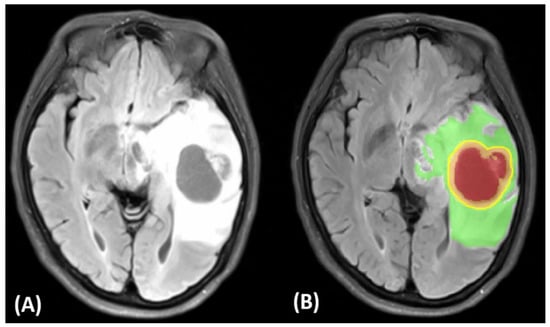

3.1. Ground Truth Segmentation and Identification of Tumor Habitats on MRI